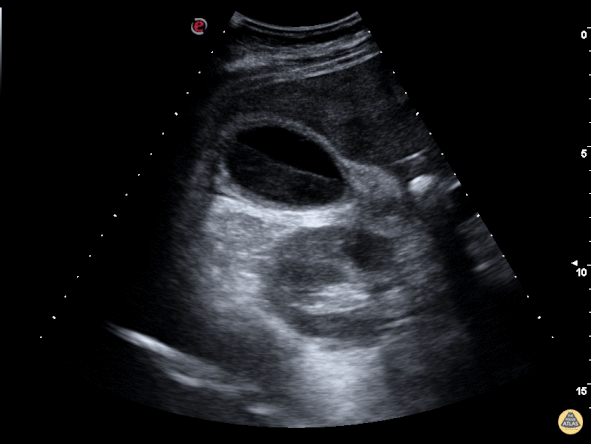

Biliary - Gallbladder with Biliary Sludge

The image above is from a patient presenting to the emergency department with recurrent abdominal pain. The image demonstrates a large amount of biliary sludge within a normal sized gallbladder. Biliary colic from intermittent obstruction was suspected. While the gallbladder wall is noted to be mildly thick here, cholecystitis was ruled out based on other clinical factors. Marco Garrone, MD - Torino, Italy